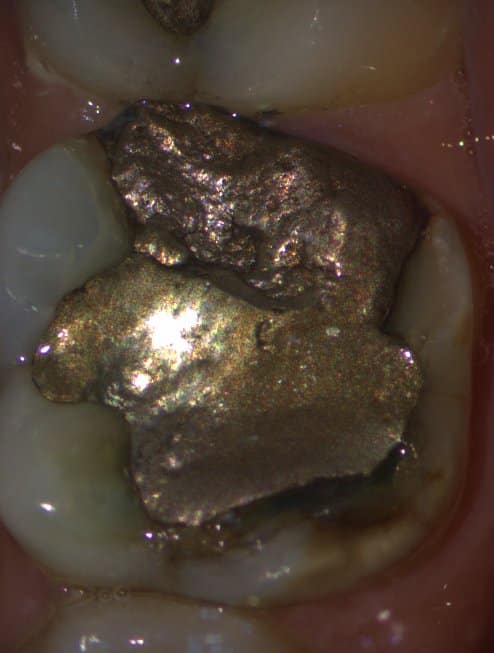

The patient complained of pain in the first mandibular molar during biting. This tooth showed an unacceptable amalgam restoration with caries underneath and a crack at the mesial side.

Pre Operative